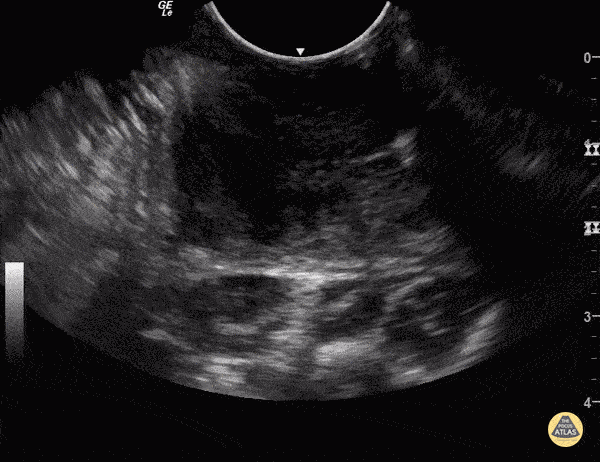

Soft Tissue - Peritonsillar Abscess

Some people like to know what they're aiming at before they stick needles in the back of people's throats. You can use an endocavitary probe for an intraoral approach... to make sure it's not just cellulitis. Your patient will thank you. As with any abscess, look for a relatively hypoechoic circumscribed area representing a collection of fluid. Sukh Singh, MD Caption: Matthew Riscinti, MD